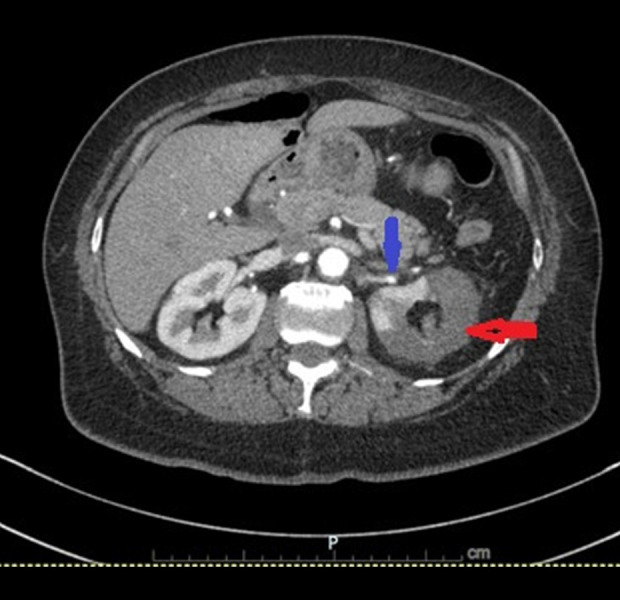

BACKGROUND Renal infarction is a rare condition resulting from interruption of renal arterial blood flow. Its nonspecific presentation often mimics more common diagnoses such as nephrolithiasis, pyelonephritis, or musculoskeletal pain, contributing to delayed or missed diagnosis. Early identification is essential to prevent irreversible renal damage and optimize patient outcomes. Imaging plays a critical role in both the initial diagnosis and in determining the underlying etiology, which may include thromboembolism, in-situ thrombosis, vascular injury, or hypercoagulable states. CASE REPORT We describe a case of a 63-year-old woman with a history of coronary artery disease, diabetes mellitus, hormone replacement therapy, and a 42 pack-year smoking history, who presented with sudden-onset, severe left-flank pain. Initial laboratory results were nonspecific, with mild proteinuria and microscopic hematuria. Computed tomography (CT) angiography demonstrated severe stenosis of the superior left renal artery and extensive left renal infarction. A diagnosis of atherosclerotic renal infarction was made. She was treated with intravenous heparin, transitioned to dual antiplatelet therapy and high-intensity statin, and discharged with a 30-day cardiac event monitor. No arrhythmia was detected, and her thrombophilia workup was negative. Follow-up CT angiography 1 month later revealed complete resolution of the renal artery stenosis, with no residual narrowing or plaque. The transient nature of the vascular finding, along with the lack of structural atherosclerosis, prompted diagnostic reassessment, favoring an embolic mechanism possibly related to multiple modifiable prothrombotic clinical risk factors and unrecognized embolic sources. CONCLUSIONS This case illustrates the importance of follow-up imaging and clinical reassessment in differentiating embolic from atherosclerotic causes of renal infarction.